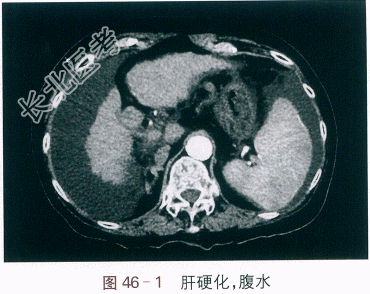

B超检查示:肝硬化,脾大,腹水(下腹部65mm);腹部CT检查示:肝硬化,腹水,门静脉高压,门静脉血流通畅。如图46-1所示。